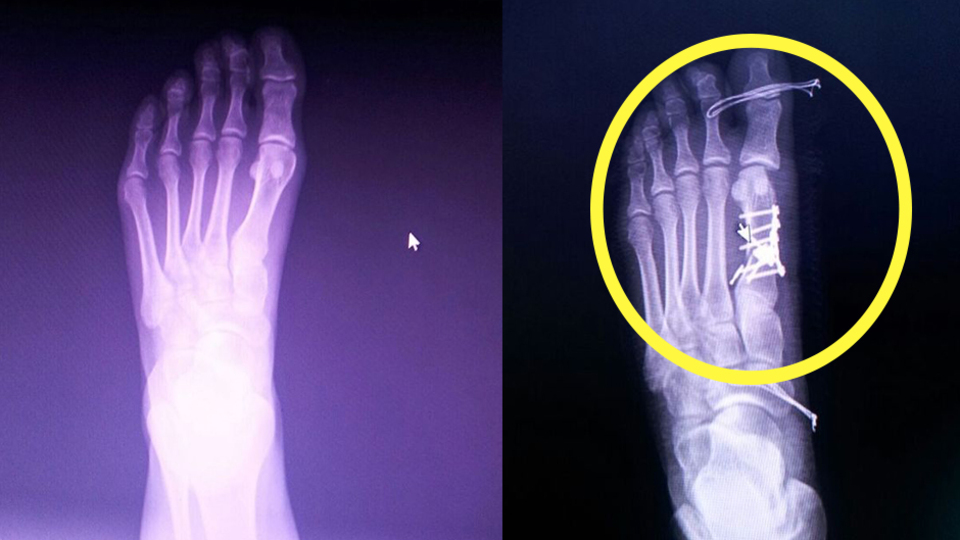

İddiaya göre, İstanbul'da ikamet eden memur Büşra Nergiz, sol ayak parmaklarının birindeki nasır nedeniyle ailesinin yaşadığı Yalova'ya gelerek Devlet Hastanesi Ortopedi ve Travmatoloji Bölümüne müracaat etti. Nergiz , Opr. Dr. Ö.A. tarafından muayene edildi. Röntgeni çekilen Nergiz'in sol baş parmağının yanındaki parmağında kırık olduğu teşhis edildi.

AA'nın haberine göre; 13 Temmuz'da Ö.A. tarafından aynı hastanede ameliyat edilen Nergiz'in kırık parmağının yerine sağlam sol ayak baş parmağının ameliyat edildiği ve 5 platin takıldığı belirlendi. Bunun üzerine Büşra Nergiz, Cumhuriyet Savcılığına suç duyurusunda bulunurken, şikayet üzerine hastane yönetimi Dr. Ö.A. hakkında idari soruşturma başlattı.

Ben de 'Narkoz almıştım zaten, 3 gün sonra tekrardan narkoz almam doğru mu? O zaman ikisini aynı anda yapsaydınız.' dediğimde, o da 'Pazartesi gel istersen yapalım, istersen 6 ay sonra gel bir daha yapalım işlemini' diye yanıt verdi. Bu şekilde umursamaz bir tavırla çıktı gitti. 4-5 gündür ayağımın üstüne basamadığım için yerimden kalkamıyorum. Ayağıma 5 platin takılmış. Bundan da haberimiz yok. Hastaneden taburcu olduğum gün öğrendim. Platin takılacağına dair bir şeye imza atmadık. Sormadı. Sağlam ayağıma platin takılması beni yordu. Şu anda ayağıma ne olacağını bilmiyorum. Hasar kalacak mı? Yürümem de herhangi bir şekilde sıkıntı olacak mı? Onu da bilmiyorum."